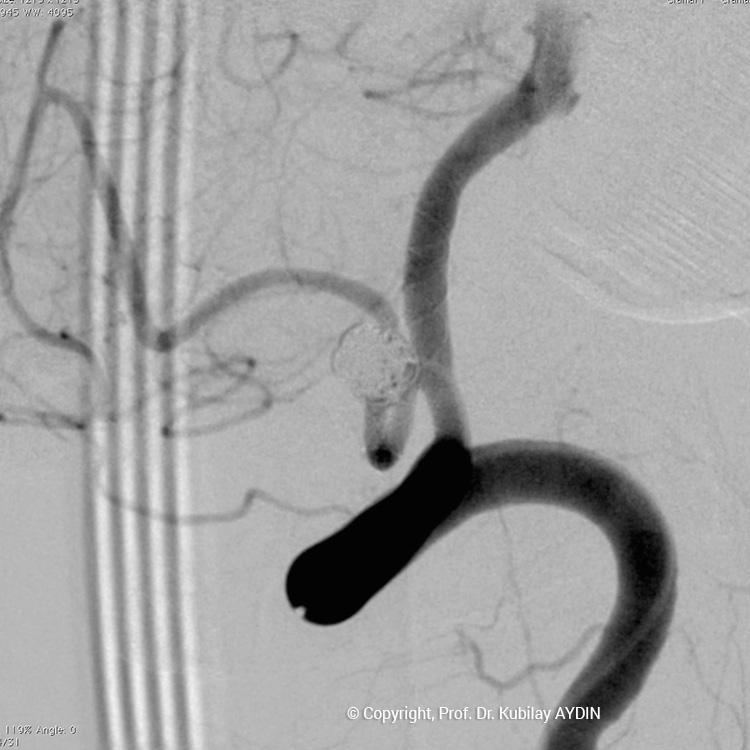

Tüm kapalı anevrizma tedavileri, hasta genel anestezi ile uyutularak gerçekleştirilir. Kapalı anevrizma tedavisinin tüm aşamaları, bacak atardamarı içine yerleştirilen 2 mm çaplı (kurşun kalemden daha ince) bir özel kateter yoluyla uygulanır. Bu küçük giriş noktasından damar içine çok ince (0.5mm çapında) ve yumuşak yapıda mikrokateter adını verdiğimiz özel plastik tüp gönderilir. Anevrizmayı kapatmak için kullandığımız bu mikrokateter, anjiografi cihazında izlenerek anevrizmanın bulunduğu damar içine yönlendirilir. İçi boş, çok ince ve yumuşak bir plastik tüp şeklinde olan mikrokateterin ucu, anevrizma kesesi içine yerleştirilir. Daha sonra bu mikrokateter içerisinden gönderilen platinden yapılmış çok yumuşak “koil” adı verilen tellerle anevrizma kesesi doldurulur. Koiller, anevrizma kesesi içinde bir yumak oluşturup, anevrizma içine kan girişini engeller. Anevrizma kesesi, koillerle tamamen doldurulup, anevrizma içine kan girişi tam olarak durduğu zaman, mikrokateter anevrizma içinden geri alınarak işlem tamamlanır. Anevrizmanın koil adı verilen özel tellerle doldurularak kapatılma işlemine, "koilleme" adı verilir. Anevrizmanın koillenerek kapatılması işlemi, oldukça güvenli ve etkili bir tedavi yöntemidir. Kanamamış beyin anevrizması olan hasta, koilleme yöntemi ile tedavi edildikten 1-2 gün sonra hasta normal günlük yaşamına dönebilir.

Anevrizma kesesinin damarla birliştiği noktasına, “anevrizmanın boynu” denir. Boynu geniş olan anevrizmaların tedavisinde, anevrizma içine konulacak koillerin, anadamar içine sarkmaması için yardımcı cihazlar kullanmak gerekebilir. Geniş boyunlu anevrizmaların koillenmesi sırasında özel yapıda balonlar veya stentler (metal kafes) kullanmak gerekebilir.

Geniş boyunlu anevrizmaların stent kullanılarak koillerle kapatılması işlemine “stent-yardımlı koilleme” adını veriyoruz. Bu işlemin ilk aşamasında anevrizmanın boynunu örtecek şekilde damar içine bir metal kafes (stent) yerleştirilerek, bir sonraki aşamada anevrizma kesesi içine konulan koillerin damar içine sarkması önlenir. Yani, burada stentin görevi, anevrizma içine doldurduğumuz koil adı verilen tellerin, damar içine sarkmasını önlemektir. Stent-yardımlı koilleme, geniş boyunlu anevrizmaların kapalı yöntemle tedavisinde tercih edilen bir yöntemdir.